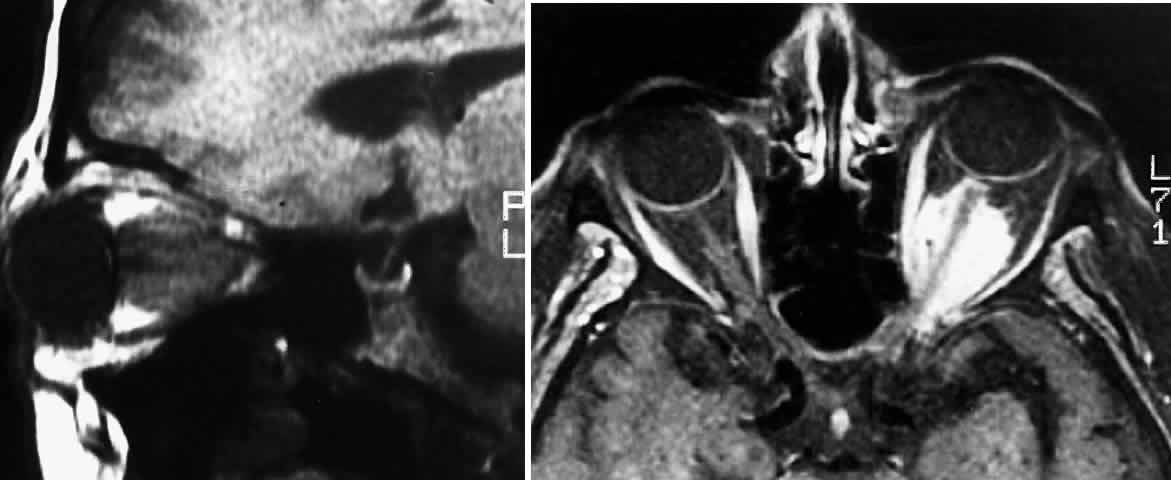

Fig. 5. A. T1-weighted oblique MRI of the orbit, demonstrating an optic nerve glioma. B. Contrast-enhanced T1-weighted axial MRI of the orbit, demonstrating left meningioma with intracanalicular extension.

Globular tumors in the suprasellar area that lack these features usually require craniotomy and biopsy confirmation. Lesions that may be difficult to distinguish from optic pathway gliomas include germinomas of the visual system and optic nerve choristoma because they both may appear intrinsic to the visual pathway.13 Tumors such as craniopharyngiomas and pituitary adenomas usually do not appear intrinsic to the visual pathway and may have features of sellar enlargement. Findings such as enhancement of the leptomeninges or peripheral enhancement of an enlarged chiasm are atypical of optic glioma and may indicate an inflammatory process masquerading as a glioma.83 Aneurysms in the suprasellar area may sometimes appear on neuroimaging to be intrinsic to the visual pathway. Better definition may be noted with magnetic resonance angiography.13 In contrast to orbital optic nerve gliomas, meningiomas enhance strongly with gadolinium and are less common in children. Meningiomas have the following features on axial CT scanning that are not typically shared by optic nerve gliomas:

5. Calcification84 (Fig. 5 A and B)